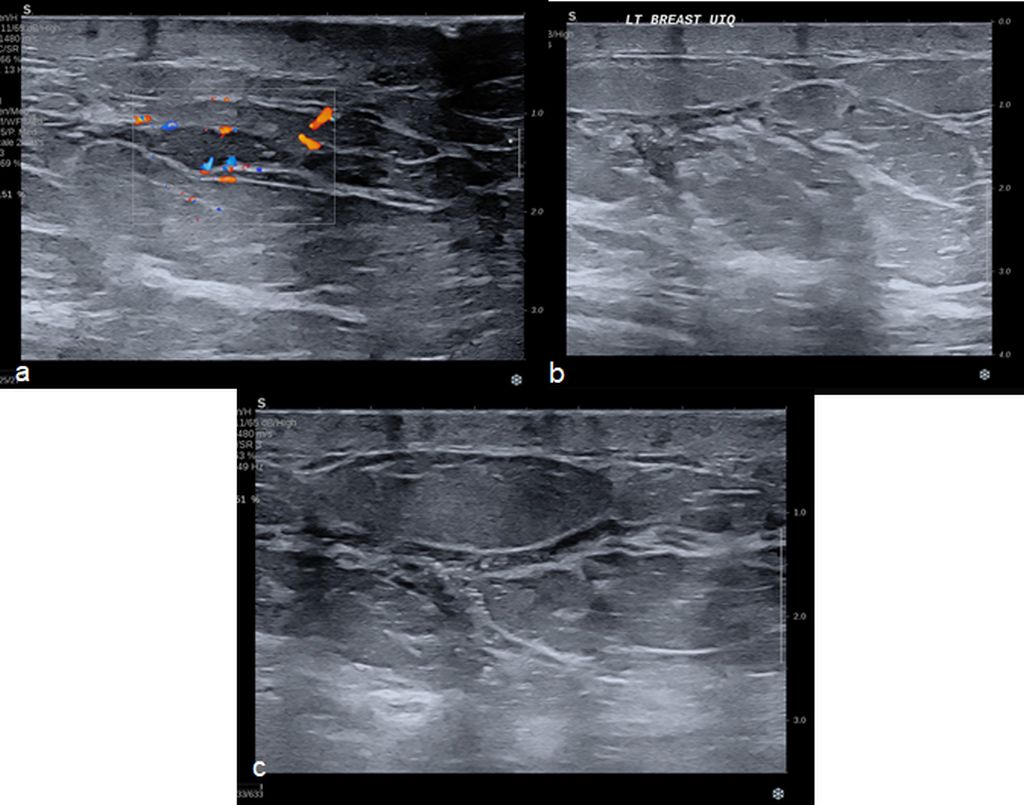

Low energy 2D mammogram images of both breasts in CC and MLO views (figure 1) demonstrate focal asymmetry with architectural distortion in the upper central quadrant of the middle third in the left breast with associated architectural distortion. Fine pleomorphic calcifications in regional distribution are noted in the inner central and upper inner quadrants of the left breast (figure 2). Diffuse skin and trabecular thickening is noted in the left breast. On post contrast recombined images (Figure 3), the area of focal asymmetry shows a heterogeneously enhancing mass with washout on delayed image (MLO). Heterogeneous and clumped non-mass enhancement in diffuse distribution is noted involving the areas of calcifications in the inner quadrant (red circle in figure 4) which could represent calcified ductal carcinoma in situ (DCIS) as well in the outer quadrant (green circle in figure 4) which could represent non-calcified DCIS. To differentiate between non-mass enhancement in diffuse distribution and background parenchymal enhancement, comparison with the opposite breast should be done. In our case there is minimal background parenchymal enhancement in the right breast (figure 3a and 3c) whereas clumped enhancement in diffuse distribution in the left breast (figure 3b and 3d) suggestive of non-mass enhancement in the left breast. Ultrasound correlation revealed an irregular isoechoic mass with indistinct margins with no posterior features measuring 2.2x1.9x1.6cm at 11:30 O'clock position, 6cm fn in left breast. It is hard on elastography (Figure 5). Non-mass ductal abnormalities in the form of irregular prominent and dilated ducts filled with soft tissue and echogenic foci within are noted in upper inner, lower inner and upper outer quadrants of left breast (Figure 6). The whole abnormality extends from the 8-12-3 o'clock position of the left breast. On tomo slices two equal density lesions with indistinct margins are noted in the upper outer quadrant of the right breast. On post contrast recombined images, they show heterogeneous enhancement. Ultrasound correlation revealed two hypoechoic lesions with circumscribed margins in the upper outer quadrant. Multiple enlarged left level I and level II lymph nodes are noted, which show asymmetrical cortical thickening and loss of fatty hilum (figure 7). MRI post contrast subtraction axial images (figure 8a and b) revealed a lesion with irregular shape and margins in the upper central quadrant of left breast with associated non-mass enhancement in diffuse distribution in upper inner, upper outer and lower inner quadrants confirming the mammographic extent of abnormalities (figure 8c).